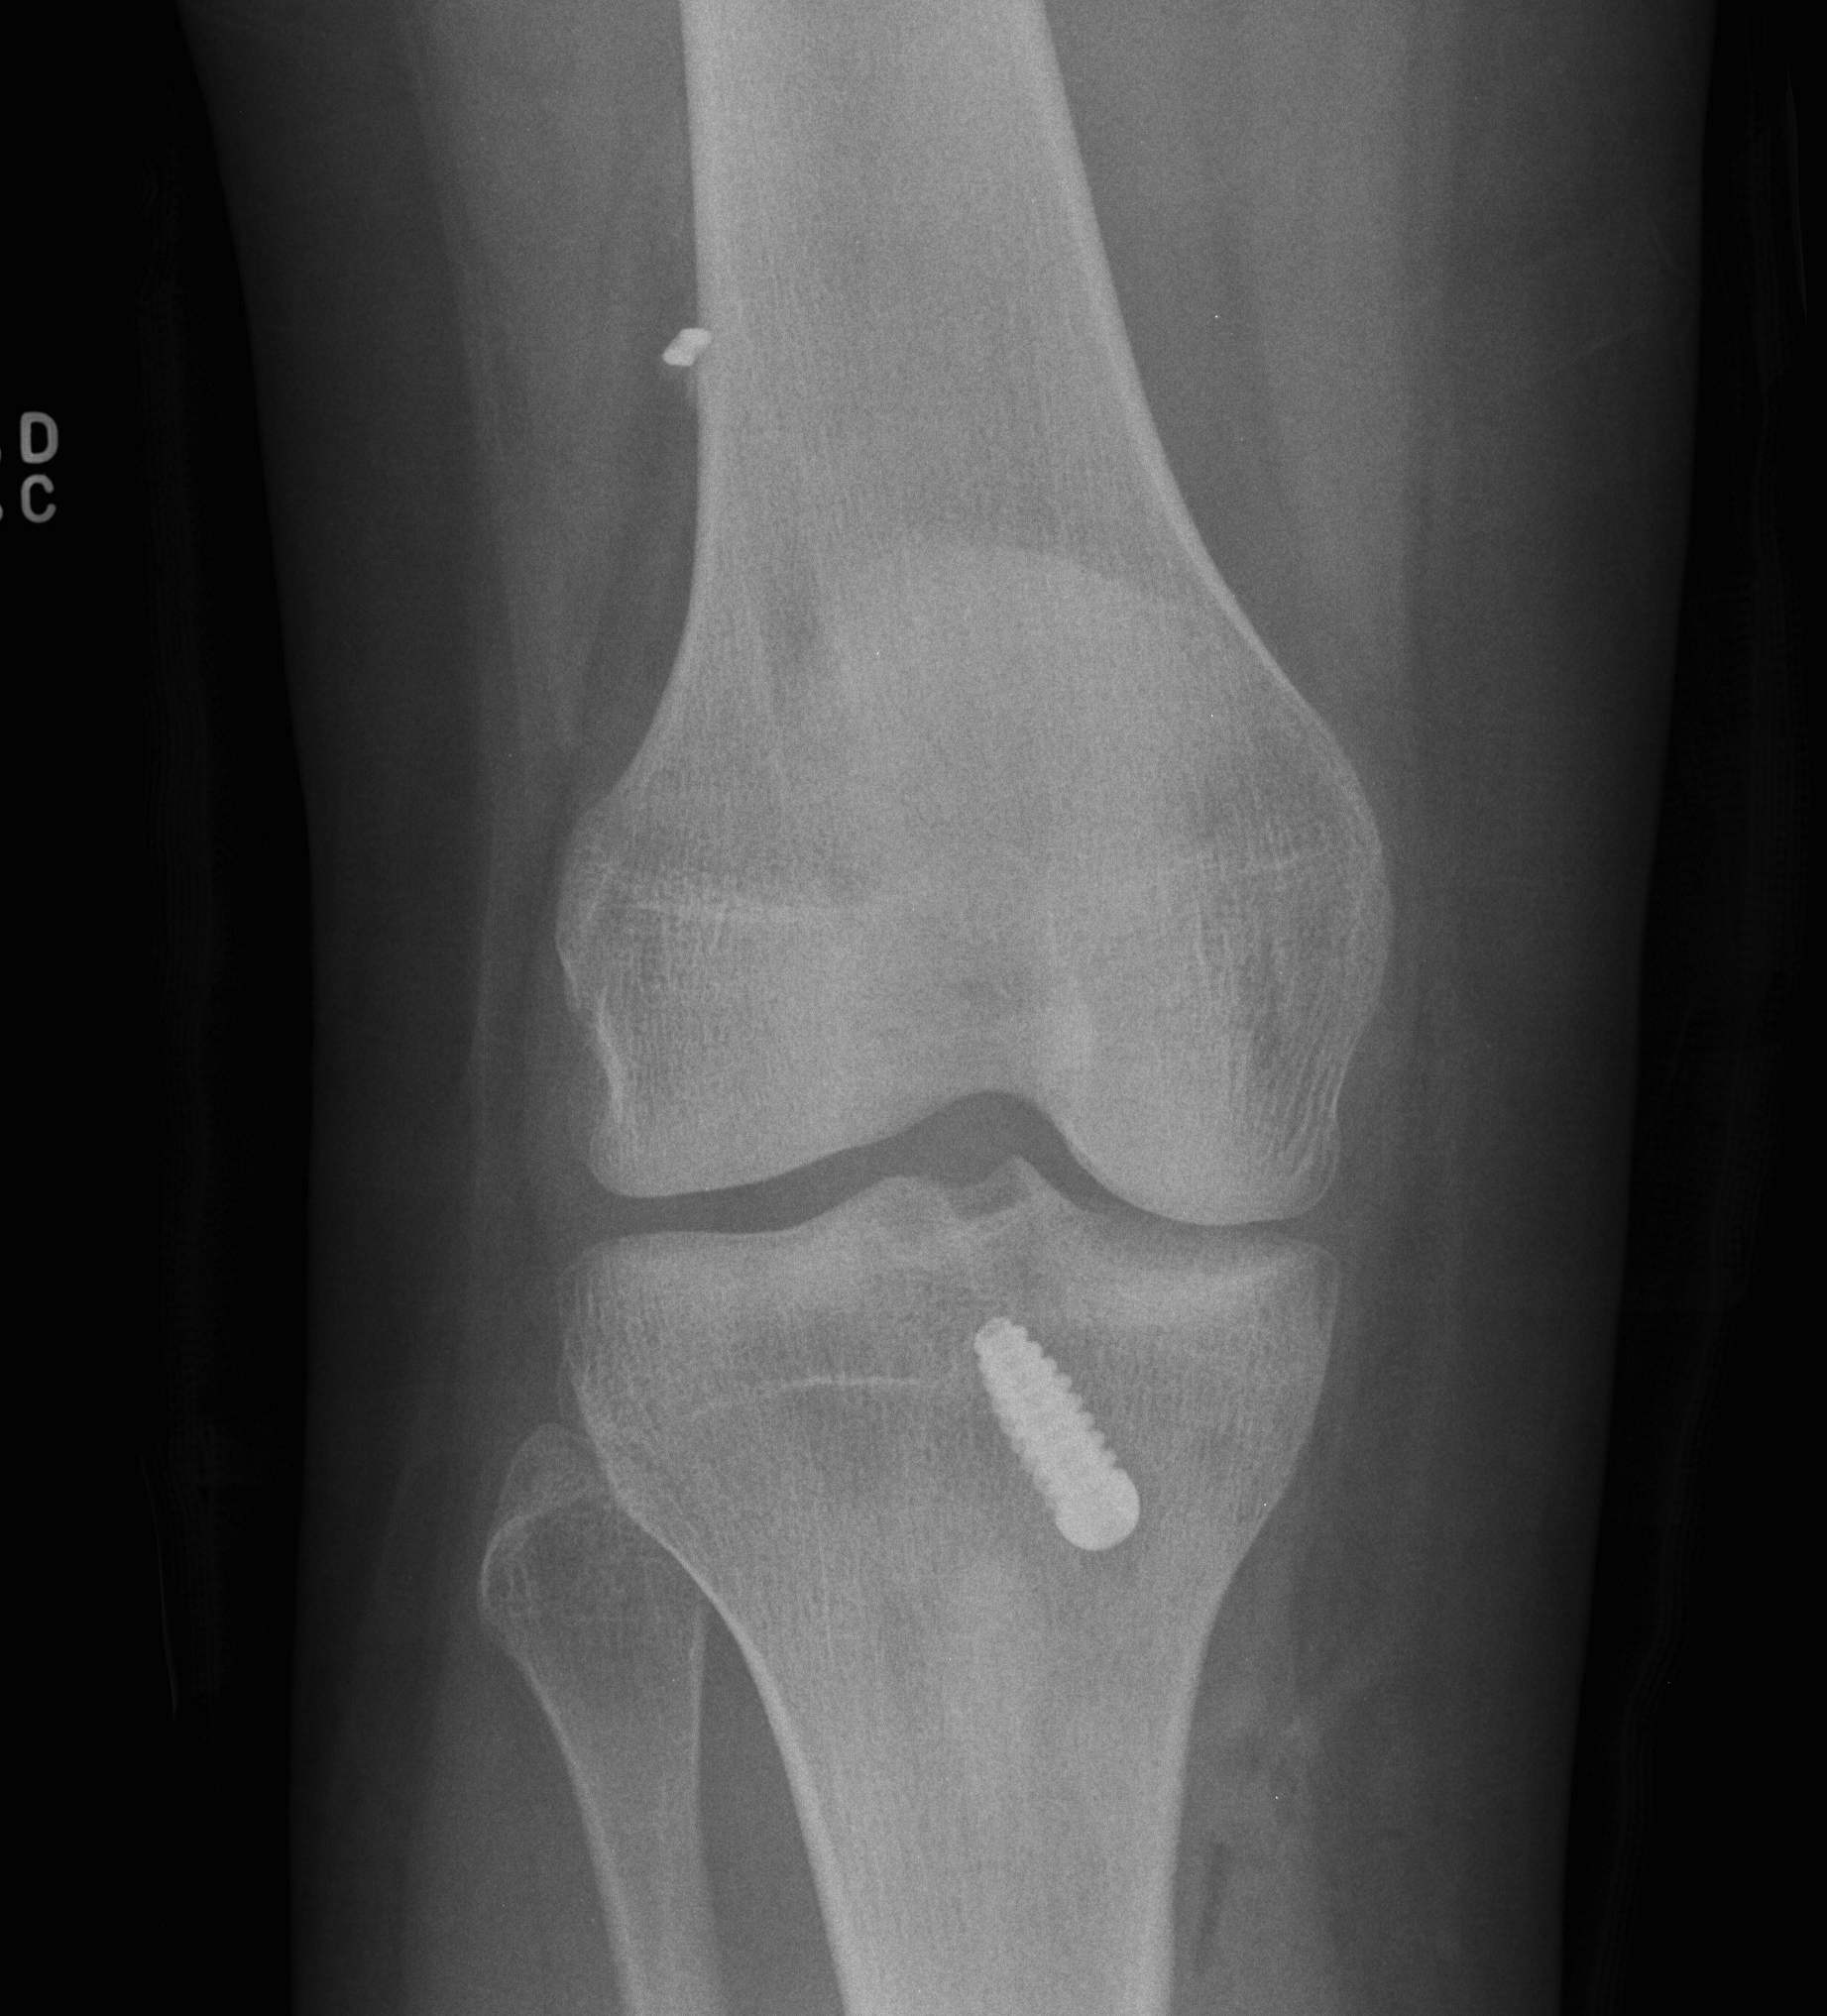

Tibial fixation

Place beath wire and pass RCI screw anteriorly

- usually 8 or 9 mm for men and women

- the tibial bone is soft

- will usually take a 25 mm screw / up to 35 mm

- +/- supplemental post / screw / staple